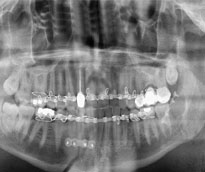

Ortodonti

Oral Diagnoz ve Radyoloji